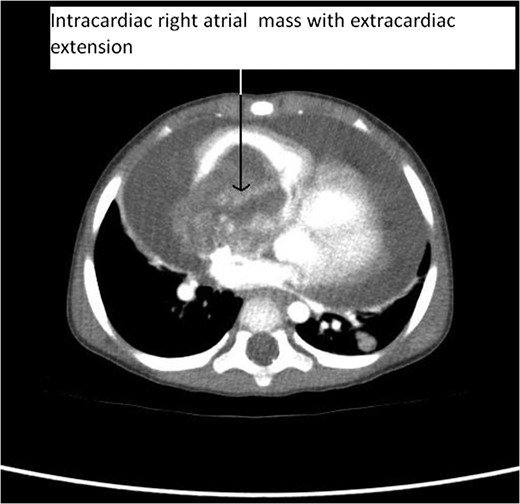

CT Thorax showing intracardiac right atrial mass with extracardiac extension.